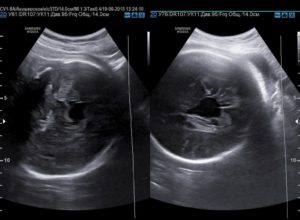

Киста в области сосудистого сплетения, расположенного в желудочковой системе в головном мозге у плода, обычно обнаруживается на 20 неделе беременности в ходе УЗИ-обследования. Обычно доброкачественное новообразование не представляет угрозы для жизни и здоровья малыша.

Более, чем в 90% случаев киста бесследно регрессирует на более поздних сроках гестации (до 28 недели). Редко новообразование остается неизменным, выявляется методом нейровизуализации у новорожденного ребенка и взрослого человека.

Даже в этом случае патология протекает бессимптомно, не влечет серьезных осложнений и болезней.

Киста этой локализации в мозге плода выявляется с частотой 3%.

Эхографическое ультразвуковое исследование показывает, что киста в головном мозге у плода на сроке 20 недель обычно представляет собой округлое (анэхогенное) образование, обладающее четкими контурами.

Чаще локализуется в системе боковых желудочков. Кисты в зоне сосудистых сплетений в боковых желудочках, расположенных в головном мозге у плода, бывают справа и слева, односторонними и двухсторонними, единичными и множественными.

Размеры существенно варьируются в пределах 1-15 мм в диаметре.

По неизвестным до сих пор причинам у некоторых эмбрионов возникает так называемая киста сосудистого сплетения головного мозга у плода. По факту это скопление жидкости в самом сплетении, которое выглядит на УЗИ как киста. Оно встречается с частотой от 1 до 3% всех случаев обследования беременных, иногда киста может быть односторонней или двусторонней, единичной или множественной.